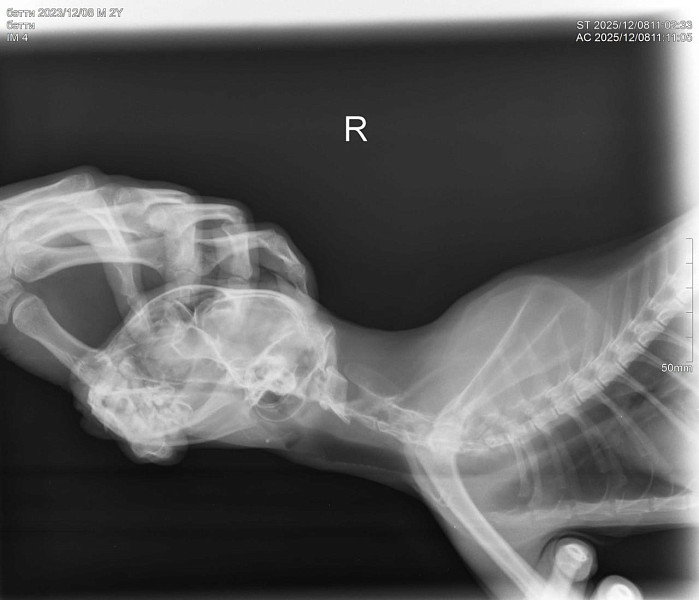

Здравствуйте! У нас кошка 10 дней находилась на улице. Через 10 дней вернулась никакая, сильное истощение, дезориентация. Кошка ходит и стукаетсях, как будто потеря в пространстве. Самостоятельно питаться не может. Повезли в ветеринарке, сделали рентген, говорят возможно ЧМТ или оттек головного мозга. Выписали препараты. Кормим со шприца, сейчас уже чуть бодрее стала, дней пять прошло после визита в ветеринару. Аппетит хороший. Но самостоятельно есть не может, зрительный рефлекс слабый. Глазки чистые.